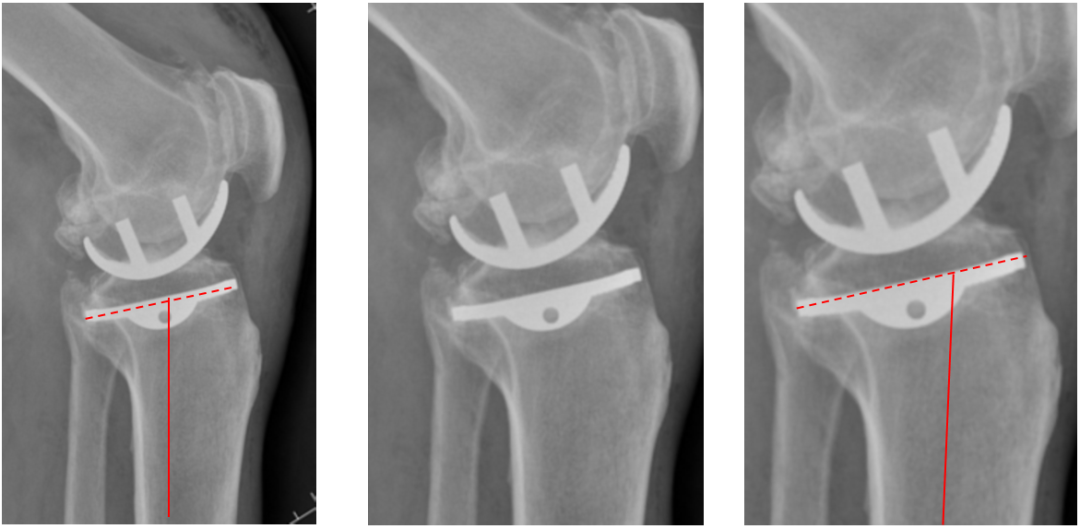

侧位片标准胫骨和股骨假体位置

侧位片假体位置:股骨假体长栓与短栓平行,后倾35°;假体后缘与股骨后髁齐平,胫骨假体后倾7°,与胫骨平台前后缘齐平。

胫骨假体偏大,且后倾不足

侧位胫骨假体位置:胫骨假体后侧悬挂>2mm,后倾2°。

胫骨假体后倾角度大

侧位片胫骨假体位置:胫骨假体后倾12°,前后缘齐平 。

股骨假体偏小

侧位片股骨假体位置:股骨假体偏小,与胫骨假体后缘不齐平;屈曲15°,未包容股骨后髁。

股骨假体偏大

侧位片股骨假体位置:股骨假体与胫骨假体不匹配,股骨假体大一个型号,屈曲45°,后缘空虚。

股骨假体屈曲角度大

侧位片股骨假体位置:股骨假体与胫骨假体匹配,股骨假体屈曲62°,前缘翘起。